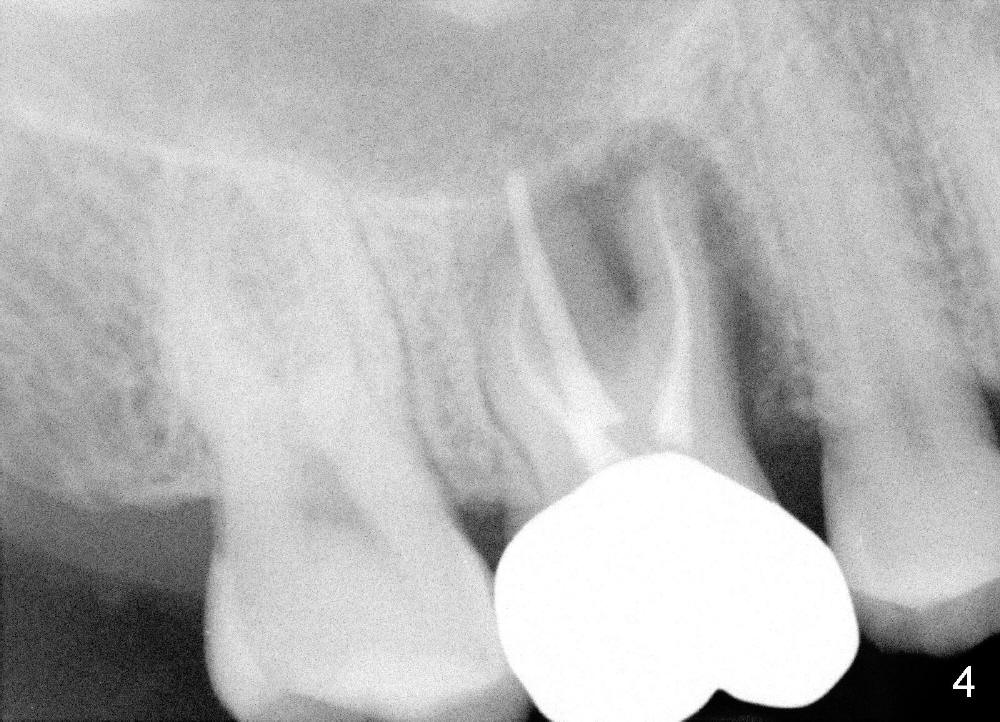

The tooth #3 of a 40-year-old man has endo failure (Fig.1-4) with resorption of the mesiobuccal plate (Fig.2). Ideally a 8x17 mm cylindrical implant is placed immediately post extraction (Fig.2,3). The patient wants to remove the tooth first and wait until his insurance gets approval for the implant coverage. No bone graft is placed in the extraction socket.